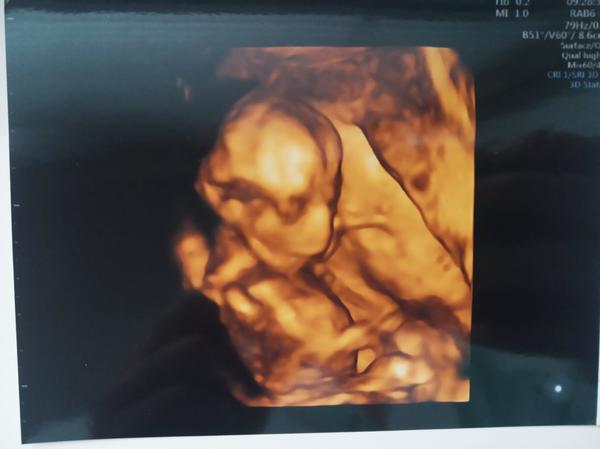

Velký nos na ultrazvuku. Máte zkušenost? A byl pak normální?

Ahoj, mám nevšední dotaz. Měli vaše miminka na fotkách z ultrazvuku velký nos a ve skutečnosti pak byl normální? Vím že mohou být ty ultrazvukové fotky zkreslené... Ano důležitější je, že je mimčo zdravé ❤️ jen mě to zajímá.

nam doktor rikal, ze pokud ma mlade na tom 3d ultrazvuku velkej nos, tak je to tim, ze pri snimani zaklonilo hlavu 🙂 ze maj jinak vsechny pidiknoflik

Mají často nos přimáčknutý, takže všelijaké patvary. Většina mimin má pidiknoflíčky pršáčky, konečný tvar se formuje po 3 letech.

Dcera měla na jednom utz místo nosu pěkný frňák a po narození po něm nebylo ani vidu. Má krásný nosík, tak se neboj. Utz muže zkreslovat ;)

Naše první holčička měla na ultrazvuku veliký nos a narodila se s krásným malým nosíkem.